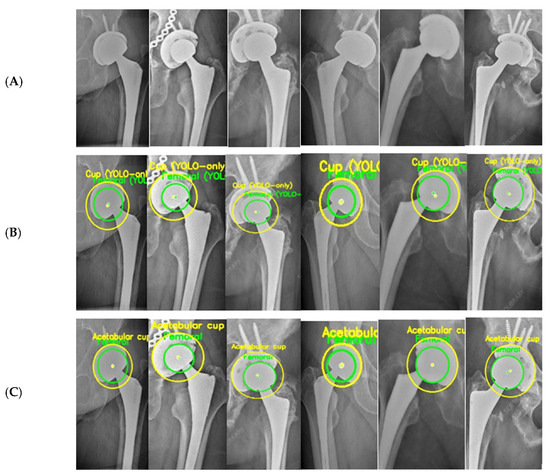

A Hybrid Automatic Model for Circle Detection in X-Ray Imagery: A Case Study on Hip Prosthesis Wear

This study presents a fully automatic hybrid framework for circle detection and geometric feature extraction from anteroposterior (AP) X-ray images. Detecting circular structures in X-ray imagery is challenging due to low contrast, noise, and metal-induced artifacts, which often limit the robustness of purely learning-based or purely geometric approaches. To address these challenges, a hybrid deep learning and computer vision pipeline is proposed that combines data-driven region localization with robust geometric fitting. A YOLOv5-based detector is first employed to identify a compact region of interest (ROI) containing circular components. Within this ROI, edge-based processing using Canny detection is applied, followed by an Edge-Snap refinement stage and robust RANSAC-based circle fitting with a Hough-transform fallback to ensure anatomically plausible circle estimation. The resulting circle centers and radii provide stable geometric parameters that can be consistently extracted across images with varying contrast, noise levels, and prosthesis appearances. The applicability of the proposed framework is demonstrated through a case study on hip prosthesis wear analysis, where the automatically detected circle parameters are used to compute medial, superior, and resultant displacement components using established two-dimensional radiographic formulations. Experimental evaluation on AP hip radiographs shows that the YOLOv5 detector achieves high ROI localization performance (mAP@0.5 = 0.971) and that the hybrid pipeline produces consistent circle parameters across longitudinal image sequences. Overall, the proposed method provides an end-to-end automatic solution for robust circle detection in X-ray imagery, with hip prosthesis wear presented solely as a case study without clinical or diagnostic claims. Full article